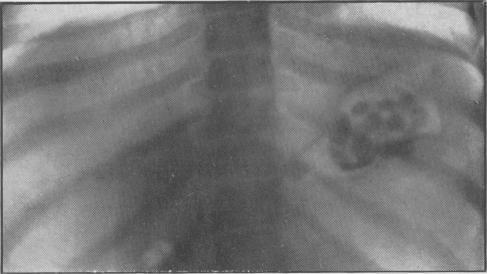

Generalized retardation, with renal impairment, hypercalcaemia and osteosclerosis of skull.